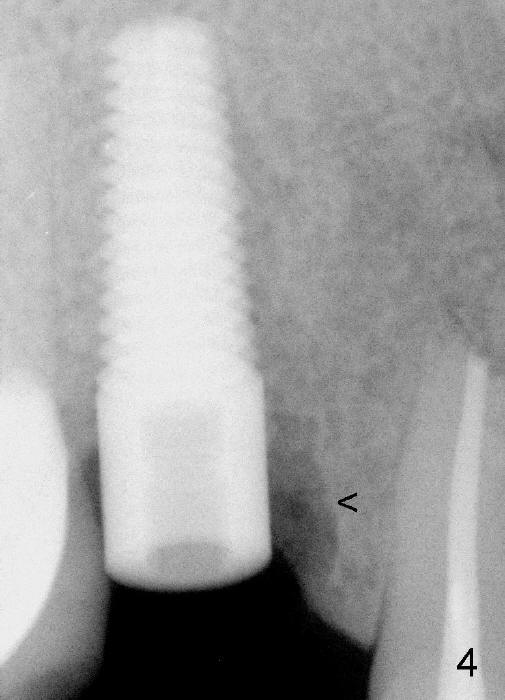

Fig.4: Immediately postop (5x17 mm implant).  <: mesial socket.